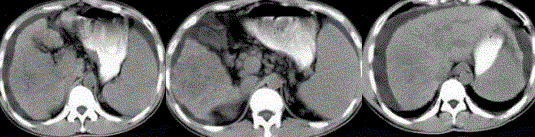

- 单项选择题男性,35岁。有乙肝病史多年, AFP阳性,影像检查如图所示, 最可能的诊断是

A、肝硬化、腹水

B、肝血管瘤

C、肝脓肿

D、肝癌、肝硬化、腹水

E、肝硬化,结节性增生